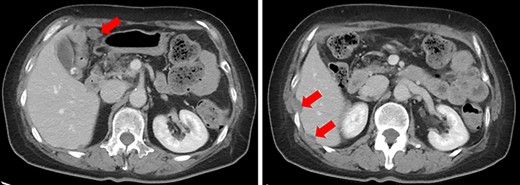

A 61-year-old woman was admitted to our hospital for examination of positive fecal occult blood test. She had a medical history of diabetes but no surgical history. Laboratory data showed that complete blood cell count and hepatic and renal functions were normal. The serum carcinoembryonic antigen level was slightly elevated to 8.7 ng/ml (reference value < 5.0 ng/ml), and the carbohydrate antigen 19-9 level was within the normal range. Colonoscopy demonstrated a Type I tumor with depression and fullness in the ascending colon, and it was VI high grade according to the Kudo pit pattern classification (Fig. 1); tissue biopsy was obtained during colonoscopy. This tumor was diagnosed as adenocarcinoma with massive submucosal invasion. Enhanced computed tomography (CT) revealed numerous nodules throughout the abdominal cavity and a small amount of ascites in the pelvic floor (Fig. 2). Ascending colon cancer could not be pointed out. Positron emission tomography and CT revealed a nodule with mild fluorine-18-fluorodeoxyglucose (FDG) uptake in the peritoneum (maximum standardized uptake value (SUVmax) = 3.0) and two nodules with mild FDG uptake (SUVmax = 3.8 and 4.1) around the liver (Fig. 3). Abnormal FDG uptake that showed the primary tumor was not found. Peritoneal dissemination of the ascending colon cancer was considered among the preoperative differential diagnoses. Based on the degree of the FDG uptake, pseudomyxoma peritonei was also differentially diagnosed.

Enhanced CT. Numerous nodules were confirmed throughout the abdominal cavity (red arrows).